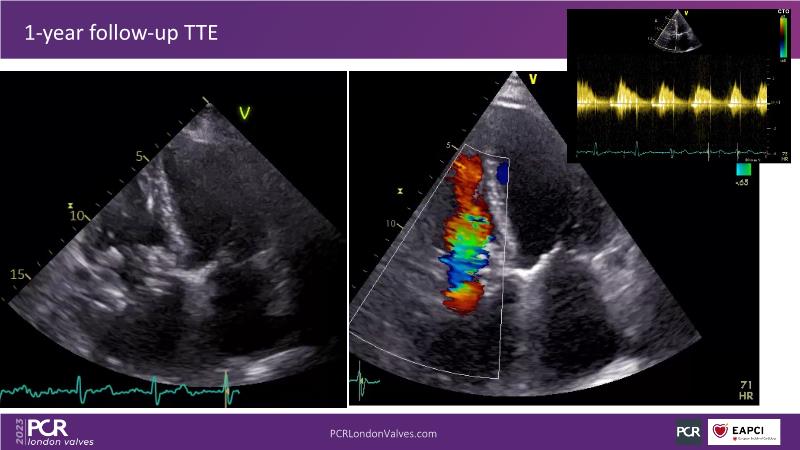

This session explores the features of the PASCAL Precision and the EVOQUE tricuspid replacement systems through simulators and case presentations, while a panel of experts discuss the technology, witnessing live demonstrations of treating mitral and tricuspid regurgitation patients.

- To learn about the differentiating features of the PASCAL Precision system showcased in a series of simulators alongside case presentations

- To interact with a panel of experts discussing the PASCAL Precision system technology and showcasing, live, its different key features in action and how they help treat mitral regurgitation and tricuspid regurgitation patients